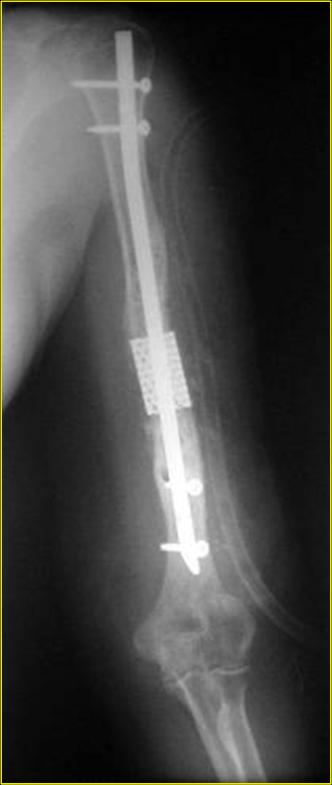

Рентгеновская версия реконструкции хронология в обратном порядке: 1,2

- через 1 год, 3,4 - 2 мес. после операции, 5,6 - после операции.

Движения в полном объеме востановлены к 2 мес. после операции. Если

надо могу  показать мультик. Сейчас уже прошло более 3 лет, больная не

показывается. Успехов ЛАФ.